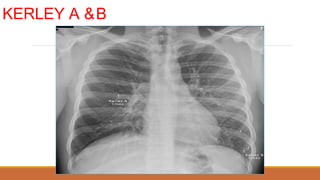

◦ KERLEY A: đỉnh, trung tâm, hình cung, dài #3-5cm, dày #3-4mm, bản chất là dày

◦ KERLEY B: đáy, ngoại biên, vuông góc màng phổi, dài #2cm, dày <2mm, bản

chất là mô kẽ ngoại biên (vách liên tiểu thùy)

◦ KERLEY C: chồng nhau của Kerley A vàB

CÁC ĐƯỜNG KERLEY

NGUYÊN NHÂN THƯỜNG GẶP NHẤT: PHÙ PHỔI

NGUYÊN NHÂN KHÁC:

◦ HẸP VAN 2 LÁ

◦ LYMPHANGITIC CARCINOMATOSIS

◦ LYMPHOMA

◦ XƠ PHỔI VÔ CĂN

◦ SARCOIDOSIS

KERLEY A &B

SUY TIM

BIỂU HIỆN TTMÔ KẼ DẠNG ĐƯỜNG: ◦ KERLEY A: đỉnh, trung tâm, hình cung, dài #3-5cm, dày #3-4mm, bản chất là dày mô kẽ trục PQ-MM ◦ KERLEY B: đáy, ngoại biên, vuông góc màng phổi, dài #2cm, dày <2mm, bản chất là mô kẽ ngoại biên (vách liên tiểu thùy) ◦ KERLEY C: chồng nhau của Kerley A vàB DẠNG BÓNG MỜ: ◦ Nốt: nhỏ, lớn ◦ Lưới, lưới-nốt, tổ ong

CÁC ĐƯỜNG KERLEY NGUYÊNNHÂN THƯỜNG GẶP NHẤT: PHÙ PHỔI NGUYÊN NHÂN KHÁC: ◦ HẸP VAN 2 LÁ ◦ LYMPHANGITIC CARCINOMATOSIS ◦ LYMPHOMA ◦ XƠ PHỔI VÔ CĂN ◦ SARCOIDOSIS